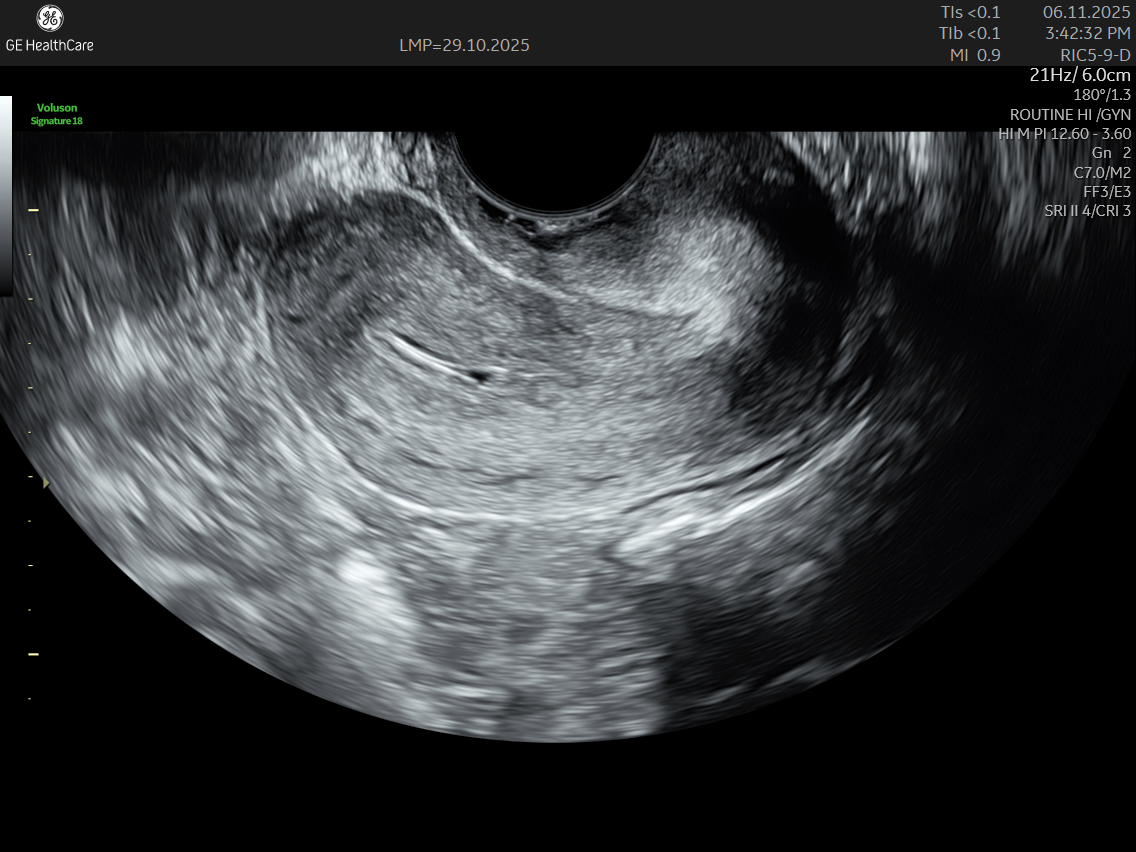

IMAGE GALLERY